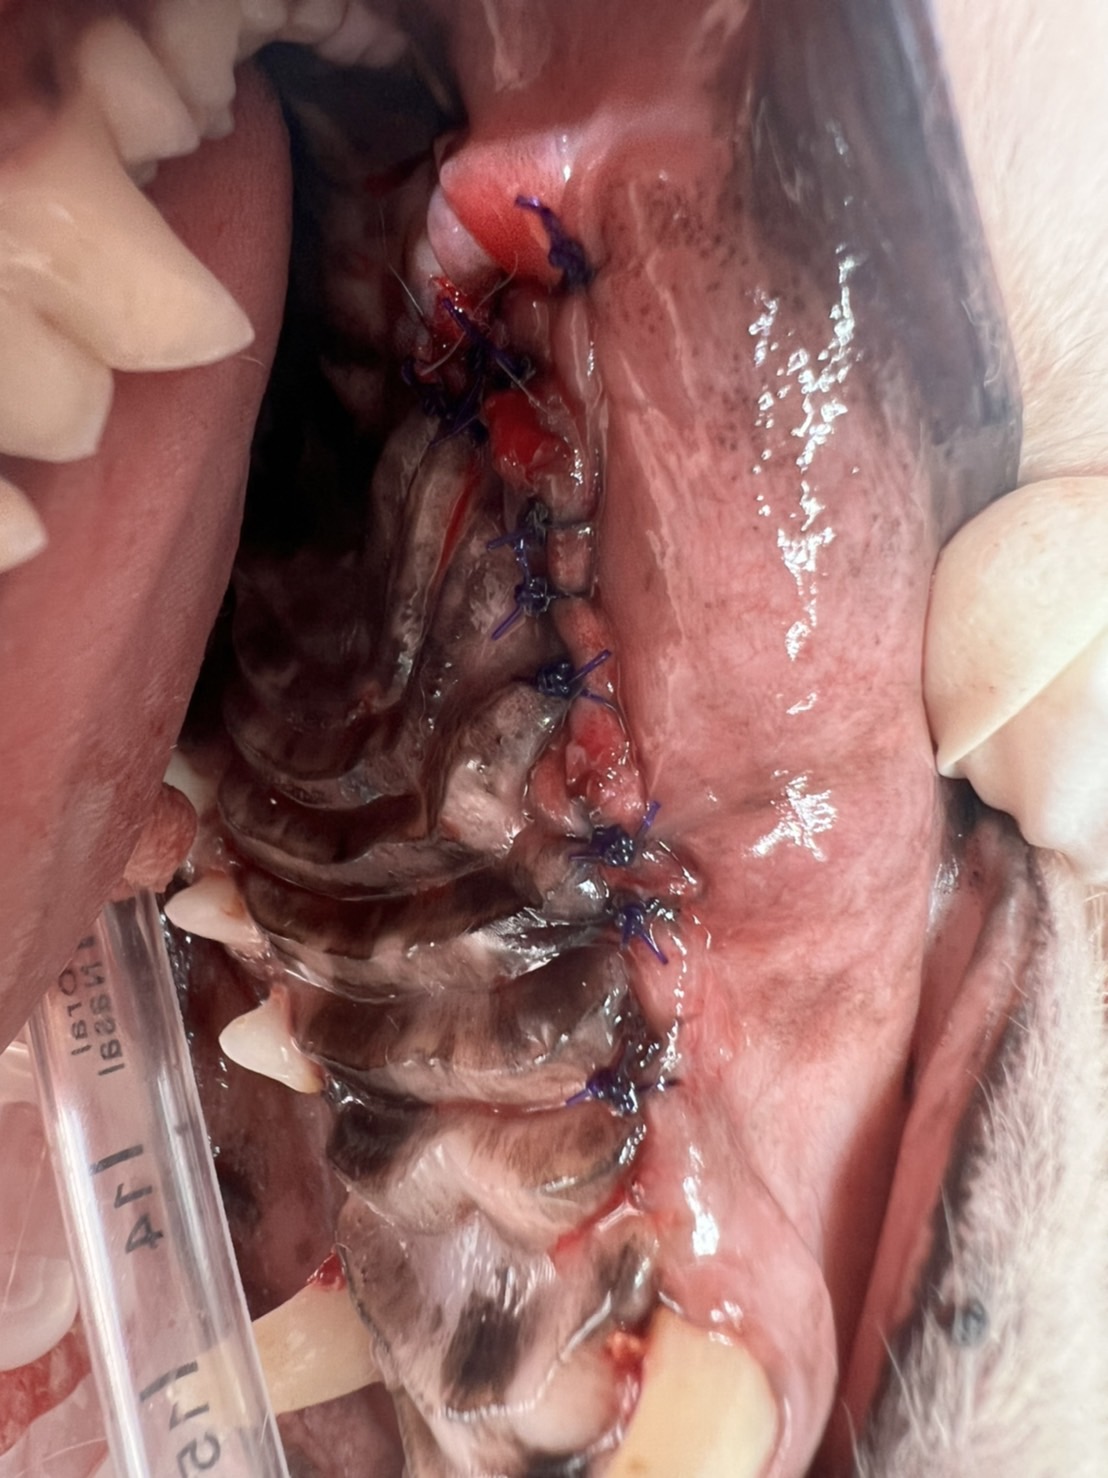

CT後にそのまま麻酔下にて抜歯を行い、鼻腔内を良く洗浄し抜歯窩を縫合しました。問題のあった臼歯はぐらつきこそなかったものの、歯周のポケットは歯槽の骨組織が吸収されてえぐれて深くなっており、周囲組織はとても脆い状態でした。